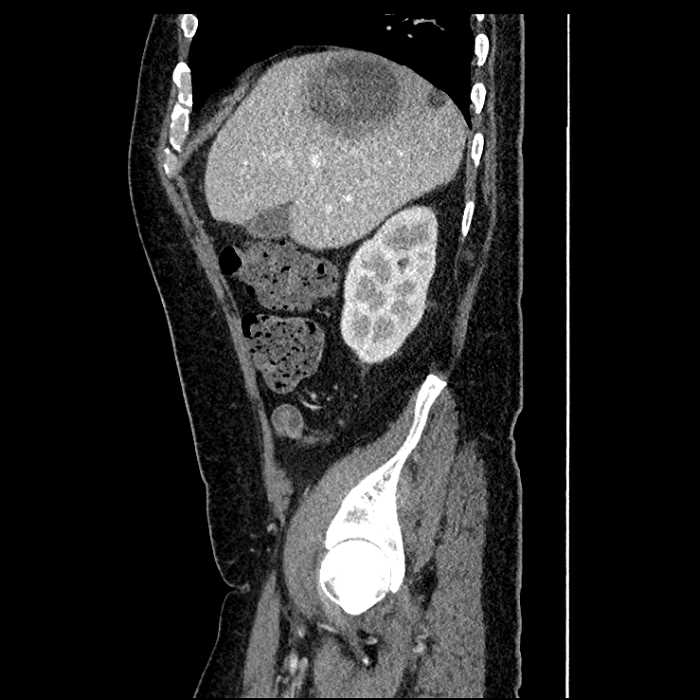

Age: 63

Sex: Male

Indication: Abdominal pain

• Large fluid density structure in hepatic segments 7 and 8 measuring 10 x 7 x 7 cm with internal septation and circumferential ill-defined low density compatible with edema

• Peripherally enhancing subcapsular collections along the anterior margin of the left hepatic lobe measuring 3 x 1 cm and 2 x 1 cm

• Clearly marginated fluid density structure in segment 7 and several other scattered tiny hypodensities, which likely represent cysts

Acute sigmoid diverticulitis complicated by a small contained perforation and a large abscess in the right hepatic lobe. Additional small subcapsular abscesses along the anterior margin of the left hepatic lobe.

• The classic CT imaging appearance is a double target sign with internal low density surrounded by an internal enhancing rim (capsule) and a low density external rim (edema)

Hepatic abscess showing the double target sign with low density internally surrounded by a thin inner enhancing rim (red arrow) and ill-defined outer low density rim (yellow arrow). Blue arrow indicates an internal septation. Red arrows: additional smaller subcapsular abscesses. Red arrow: focal contained perforation associated with diverticulitis.